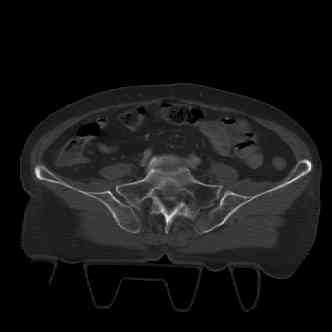

attached are images of a 70 year old female after peds versus car. her own car ran her over.

injuries are limited to the pelvis. left rami open and visible in a 10cm vertical laceration just lateral to left labia majora. wound is grossly clean. no vaginal and no urinary issues. CT scan shows widening of both SI joints anteriorly but I think this is vertically stable pattern.

pt treated that night with I/D and supra-acetabular frame to close the ring. consideration was given for SI screws bilateraly, but given time of night and other factors decision made not to proceed.

so the question is what next operatively if anything? concerns are infection, nonunion anteriorly and possible incompetence of the pelvic floor which may lead to prolapse issues. right rami are comminuted and plating may entail ilioinguinal approach to extend plate laterally to right iliac wing. retrograde screw up right rami is an option but I am not convinced it will add much. adding SI screws very doable, but major concern is restoring anterior ring. so far wound is clean and closed over a drain, and I have no plans to open it back up and wash again.

maintaining pelvic alignment in ex-fix in 70 yo female for any length of time may be challenging.

any thoughts? would anyone plate the pubic symphysis to close the gap and leave the more lateral rami fractures alone? the most recent pelvic case on this website involved pts with suprapubic catheters and antibiotic options including resorbable beads. I wonder how many people would plate and place antibiotic beads. thanks.

attached are several CT cuts. please let me know if you need more. the CT is pre-pelvic ex-fix placement.

Thank you.